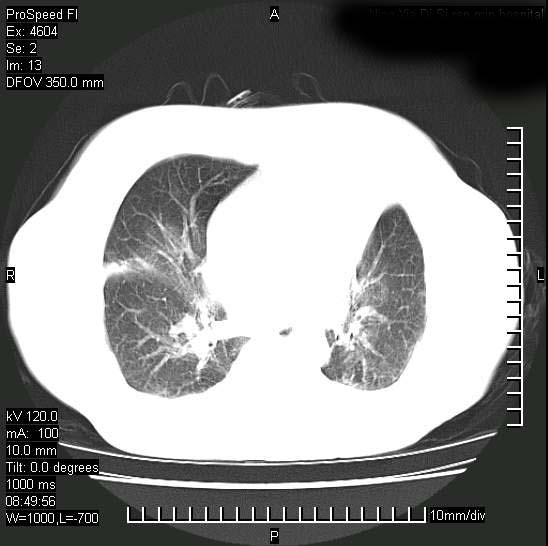

标题: CT15528:女性,79岁,近几日晚上高热,39度,仍咳少量血 [打印本页]

十几年前曾患肺结核,一周前突咳血约100ml,中性粒细胞稍高,诊断两上肺陈旧结核,下肺炎症,给予抗炎治疗,近几日晚上高热,39度,仍咳少量血,4天前ct及今天ct上传。

今天ct

短短几天内,病变范围明显增多扩大,以左侧明显,而且双侧出现胸水,还是考虑感染.

短短几天内,病变范围明显增多扩大,以左侧明显,而且双侧出现胸水,我更多考虑左侧中心性肺癌并并阻塞性不张及肺炎,炎症变化也太快了!